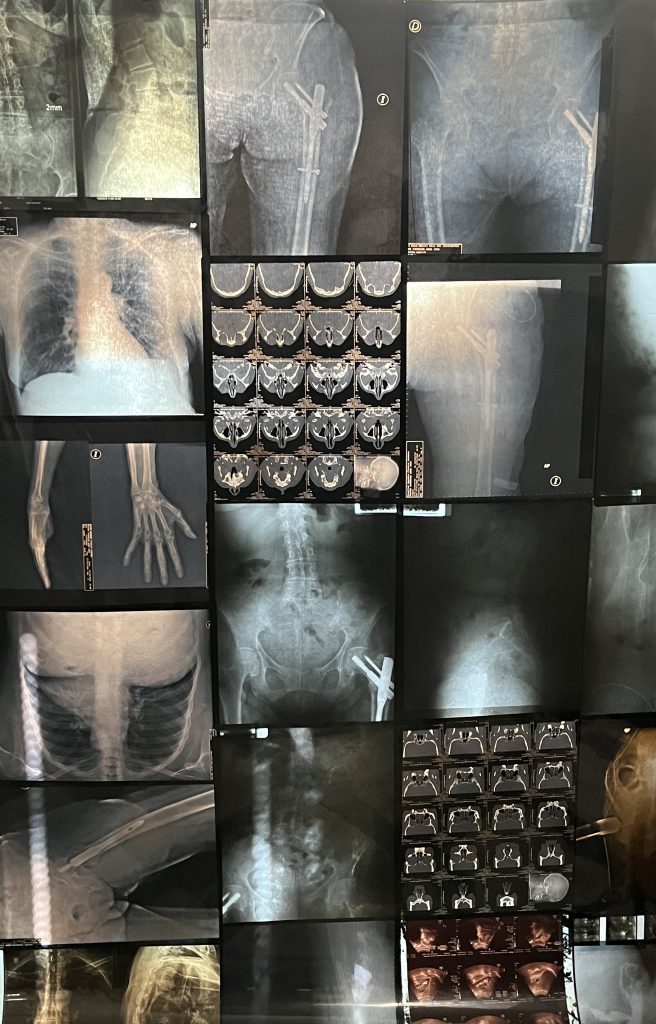

Las radiografías generalmente se guardan en expedientes médicos para uso privado de doctores y pacientes, pero el artista mexicano las reconfigura para crear una especie de vitral donde huesos, tejidos y órganos de diferentes personas flotan juntos en el espacio.

En esta obra llamada Autoradiográficas: el cuerpo interior, Héctor de Anda transforma el espacio del museo con una instalación artística, para confrontarnos con nuestro propio interior y con una realidad inevitable: nuestro cuerpo se desgasta con el tiempo. Así, la pieza transmite un dolor profundo pues retoma las imágenes frías y objetivas de la medicina y las convierte en algo sensible: huellas de heridas, marcas y experiencias vividas.